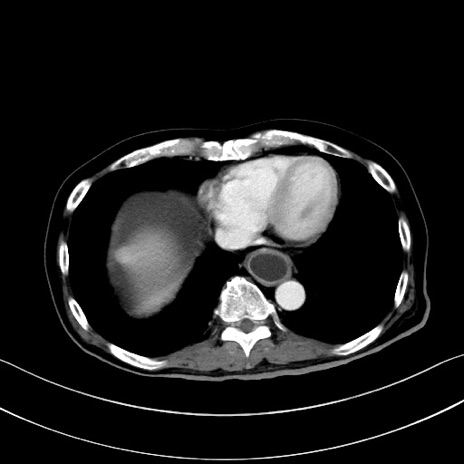

冠状断像

【症例】60歳代男性

【主訴】嘔吐

【現病歴】胃癌にて胃全摘後。食思不振が悪化し、夜中に嘔吐することがある。

【既往歴】胃癌、胃全摘、脾摘、胆摘後

【データ】WBC 5900、CRP 10.56